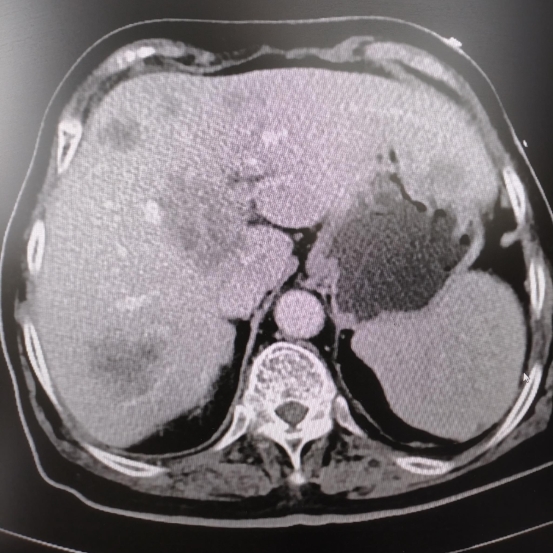

80岁的老奶奶在一年前就出现了排便异常、贫血,但因年龄较大,且伴有糖尿病、冠心病等基础疾病,忽视了这些征兆,也一直未进行肠镜检查。直到近期,奶奶症状突然加剧,已经出现严重的头晕、气喘,经检查发现重度贫血,输血后,我院肠镜检查确诊其为降结肠肿瘤,且肿瘤已导致肠道不通畅,CT进一步显示肿瘤已出现肝转移。

专家们全面分析后认为:大肠肿瘤不解决,患者将无法正常排便、进食,持续出血会加重贫血和营养不良;一旦出现肠道完全梗阻或肿瘤穿孔,治疗效果更差。与患者家属充分沟通后,团队决定先行手术切除肿瘤,解除出血及梗阻问题,待老人身体状况改善后,再针对肝转移病灶进行后续治疗。